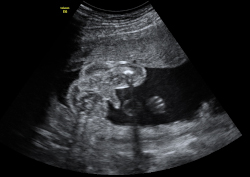

Ecografía 2D semana 20: Genitales de un niño

En la semana 20 de gestación, la ecografía en 2D muestra los genitales de un feto varón ya formados, aunque los testículos aún se encuentran alojados dentro de la cavidad abdominal. En unas semanas descenderán hasta las bolsas escrotales.

Imagen de los genitales de un niño en 2D

La imagen ecográfica en dos dimensiones es básica para obtener la imagen en 3D en tiempo casi real.